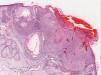

Histológicamente, se objetivó una proliferación neoplásica bien circunscrita con empalizada periférica, en la dermis superficial, en continuidad con la epidermis. Estaba constituida por células escamosas, algunas con vacuolización, con focos de queratinización y microquistes. La superficie estaba focalmente erosionada cubierta por una costra serohemática. La dermis también mostraba un infiltrado linfohistiocitario reactivo con dilatación vascular que afectaba también a la periferia de la lesión (fig. 2). Se estableció el diagnóstico de triquilemoma.

Imagen histológica (H&E, ×8). Proliferación neoplásica bien circunscrita localizada en la dermis superficial, en continuidad con la epidermis. Está compuesta de células escamosas, algunas con vacuolización, formando focos de queratinización y microquistes córneos. Nótese la epidermis ulcerada y los vasos dilatados en la periferia del tumor (flechas).